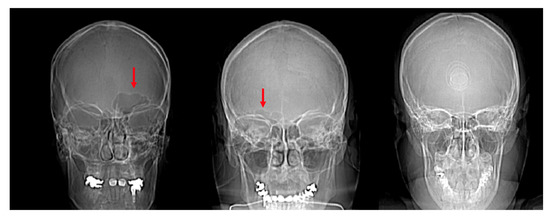

2.1. Morphological Analysis

3.1. Shape Variation Analysis

4.1. Frontal Sinus Absence and Unilateral Expression